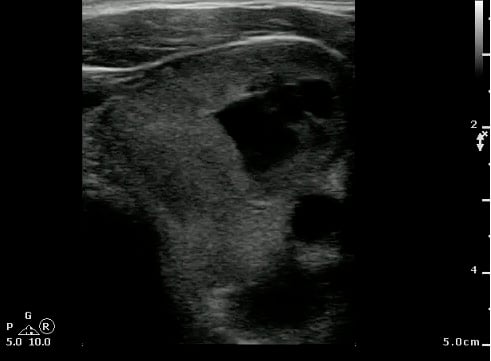

- Scanning technique20

- Probe selection:

- A 5.0 to 10.0 MHz curved array intracavitary probe is used to evaluate a suspected PTA for intraoral ultrasound. Alternatively, a high frequency linear array transducer can be used for transcervical approach, especially in children or patients with severe trismus.

- Scanning approach:

- Cover intracavitary probe with either a proprietary cover, glove or condom.

- Place probe into the oral cavity over the area in question.

- The peritonsillar area should be systematically scanned in both long and short axes.

- Color Doppler should be used to identify the depth of the carotid artery and surrounding vessels.

- Alternatively, place the linear array transducer inferior and adjacent to the angle of the mandible with rotation of the head to the contralateral side. The tonsil is deep to the submandibular gland, medial to the facial vessels, and lateral to the tongue.

- Normal findings

- Normal Tonsil

- The ovoid tonsils appear striated with hyperechoic bands and hypoechoic parenchyma, as well as lobulated margins.

- Figure 42 and 43. Normal Tonsil

Video 25. Normal tonsil